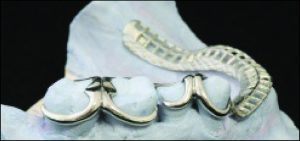

The use of direct retainers on isolated abutment teeth in distal extension PRD cases usually accelerates the destruction of the periodontium, leading to tooth loss. For this reason, it is recommended to place rests on isolated teeth and not to use direct retainers. Another option is restoration of the modification space with a fixed partial denture and splinting of the teeth (Figures 10-15).